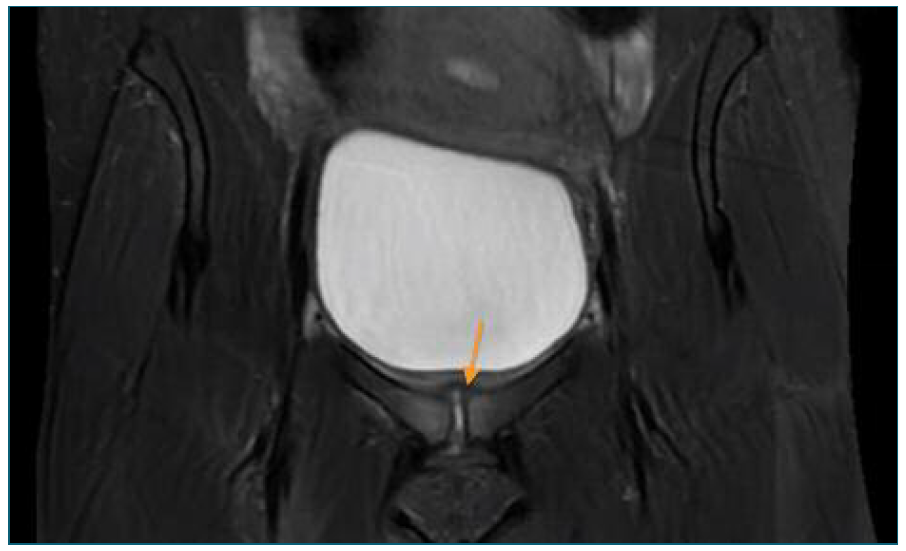

For this reason, a computed tomography (CT) was performed and showed pre-pubic soft tissues higher density and intra-articular air in the symphysis pubis (Figure 1), which led to suspicion of an osteitis. A magnetic resonance imaging (MRI) confirmed the diagnosis by showing hyperintense T2 signal and cortical irregularities on the articular surface associated with few intra-articular fluid and densifications of the soft tissues (Figures 2 and 3). At the same time, blood cultures were positive for Streptoccocus Anginosus and a puerperal osteomyelitis pubis was assumed. Antibiotic therapy was changed to intravenous benzylpenicillin (24 million Units per day), according to the antibiogram. Considering the high diagnostic certainty, based on clinical and imagological features, and technical difficulties, an aspirative biopsy was not performed. In consideration to Streptoccocus Anginosus found on blood cultures, the patient was submitted to an echocardiogram that excluded any sign of endocarditis.

Figure 3 Pelvic MRI (coronal plane) - MRI showing hyperintense T2 signal and cortical irregularities on the articular surface and densifications of the soft tissues.